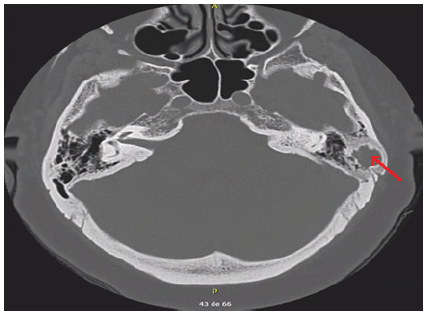

La tomografía de mastoides sin contraste (figura 2), mostró una lesión radiolúcida de bordes bien definidos a nivel de la unión entre la porción petrosa y escamosa del hueso temporal izquierdo sugerente de granuloma eosinofílico, siendo lesiones metastásicas y neoplásicas, posibilidades más alejadas.